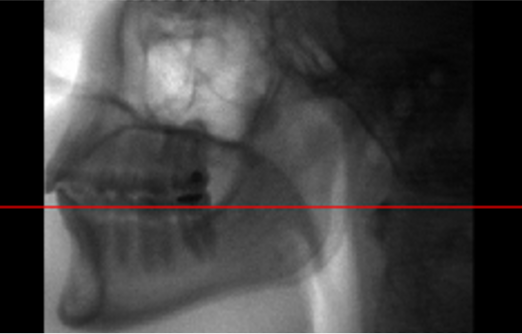

31) What does the red line represent? (1 mark)